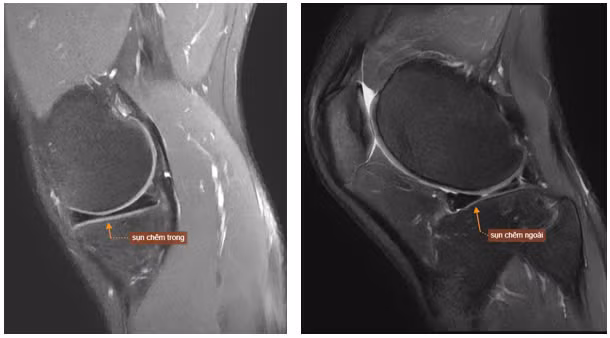

| Hình ảnh MRI khớp gối phải của bệnh nhân T.M.H cho thấy dấu hiệu rách quai xô. Ảnh BVCC |

Trên những hình ảnh cộng hưởng từ, bác sĩ và chuyên gia của Trung tâm chẩn đoán hình ảnh ghi nhận 5/6 dấu hiệu đặc trưng của rách quai xô điển hình: mất hình nơ sụn chêm, mảnh sụn rời trong khuyết gian lồi cầu, sụn chêm lật, hai sừng trước và sừng sau nhô bất thường. Hình ảnh cho thấy rách phức tạp ở thân và sừng sau sụn chêm ngoài, với mảnh sụn di lệch vào ổ khớp.